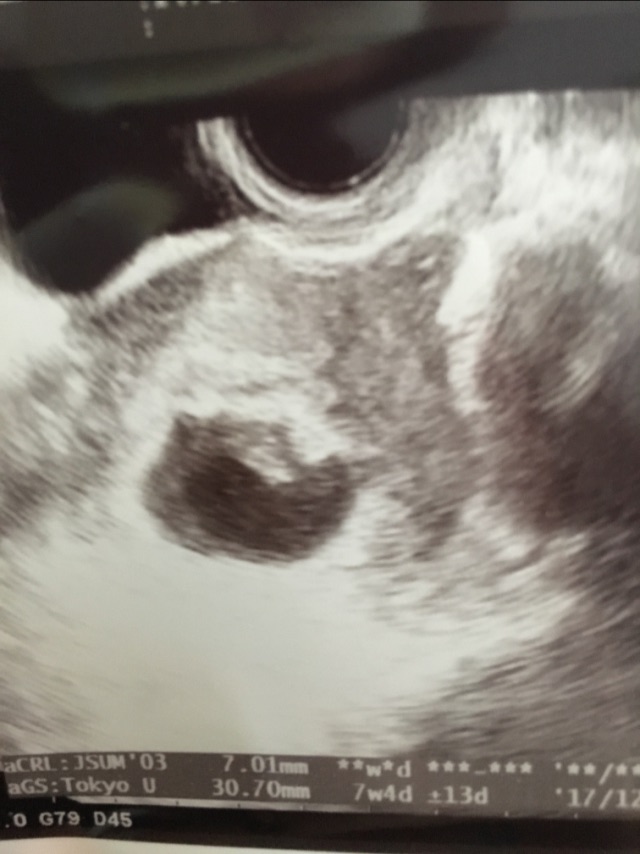

13 Weeks Sonogram Can A Baby Stop Growing At 13 Weeks causes of fetal growth restriction. intrauterine growth restriction (iugr), also called fetal growth restriction (fgr), is when the fetus is smaller than it. Fgr has many possible causes. In extreme cases, babies may. However, your pregnancy signs may continue. fetal growth restriction (fgr) is a condition where a baby is smaller than expected or when a baby’s. Can A Baby Stop Growing At 13 Weeks.